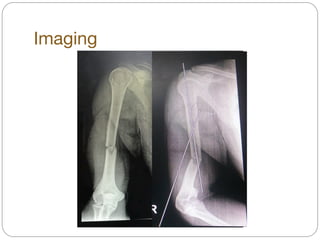

Imaging

Diagnosis

! Close fracture shaft of Rt. humerus

Film หลัง on-Uslab